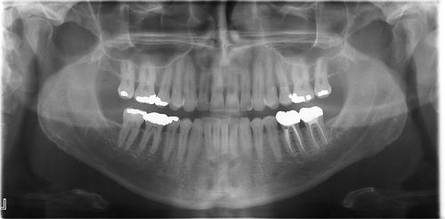

Lo Studio si avvale di tecnologie estremamente sofisticate e all'avanguardia. Le apparecchiature radiografiche a disposizione dello Studio garantiscono la tecnologia più avanzata per fornire i maggiori benefici possibili ai pazienti. Per questo motivo vengono usate radiografie digitali per produrre in modo costantemente più sicuro i risultati migliori.

La radiodiagnostica odontostomatologica (raggi X) è essenziale, quale strumento di diagnosi e prevenzione, per fornire preziose informazioni spesso non visibili durante un esame regolare dentale.Il personale infermieristico mantiene un costante aggiornamento al progresso tecnologico per offrire una vasta gamma di trattamenti da cui possiamo definire un accurato piano di cura, combinando comfort e tecnologia.